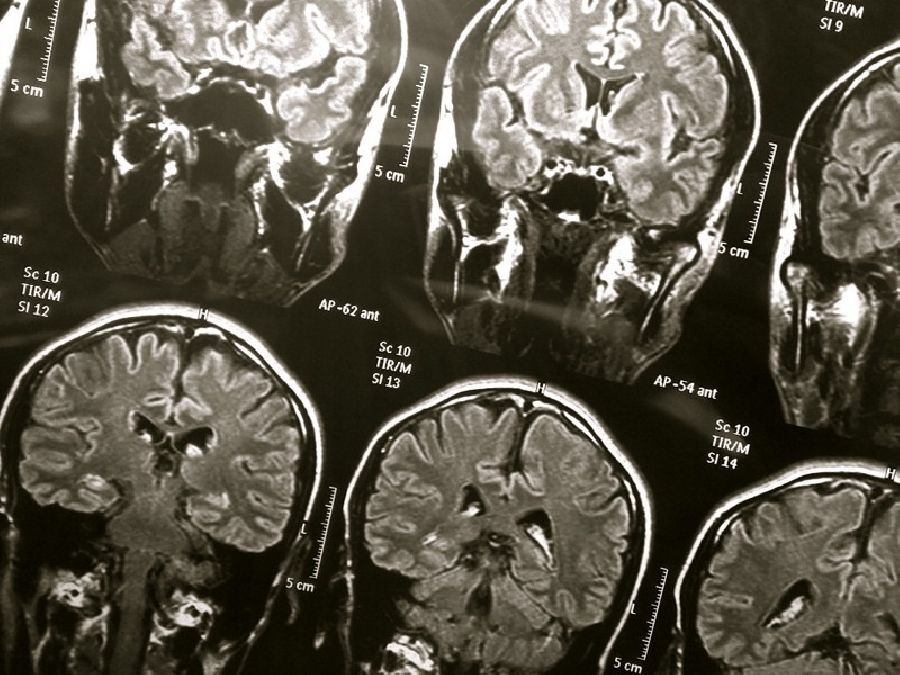

En el estudio participaron 414 personas con una edad promedio de 80 años, que realizaron pruebas cognitivas de las habilidades de pensamiento y memoria y se les evaluó la presencia de demencia al comienzo del estudio y cada dos años durante ocho años. Se sometieron a escáneres cerebrales de resonancia magnética para verificar espacios perivasculares agrandados en dos áreas clave del cerebro al comienzo del estudio y luego cada dos años durante ocho años.

La cuarta parte de las personas con el mayor número de espacios perivasculares agrandados, designados como casos graves, se comparó con aquellos con menos o ningún espacio agrandado.

Los investigadores encontraron que las personas con la mayor cantidad de espacios perivasculares agrandados en ambas áreas del cerebro tenían casi tres veces más probabilidades de desarrollar demencia durante el estudio que las personas con menos o ningún espacio agrandado.

Un total de 97 personas (24%) fueron diagnosticadas con demencia durante el estudio. De las 31 personas con casos graves en ambas áreas del cerebro, 12 personas (39%) fueron diagnosticadas con demencia.

Las personas con agrandamiento severo de los espacios perivasculares en ambas áreas del cerebro también eran más propensas a tener un mayor deterioro cuatro años después en sus puntajes generales de cognición que las personas con agrandamiento leve o ausente de espacios.

Los resultados persistieron después de que los investigadores ajustaran otros factores que podrían afectar las puntuaciones en las pruebas o el desarrollo de la demencia, como la edad, la presión arterial alta y la diabetes. Los investigadores también tomaron en cuenta otros signos de enfermedad en los pequeños vasos sanguíneos del cerebro, que también pueden ser un signo de riesgo de demencia.